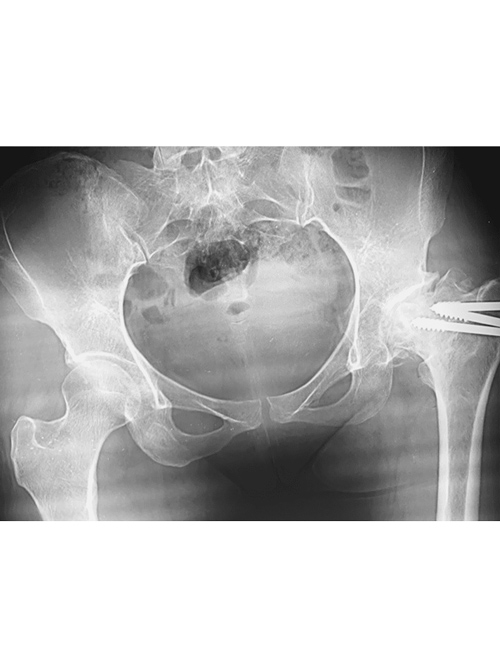

Dr. Weber and his partners participate in short term medical mission trips to Cambodia. Dr. Weber has had the pleasure of going twice now in 2018 and 2020. During these trips Dr. Weber performs total hip replacements on patients who normally would have no treatment options. To learn more and to see videos from the experience please click the links below.